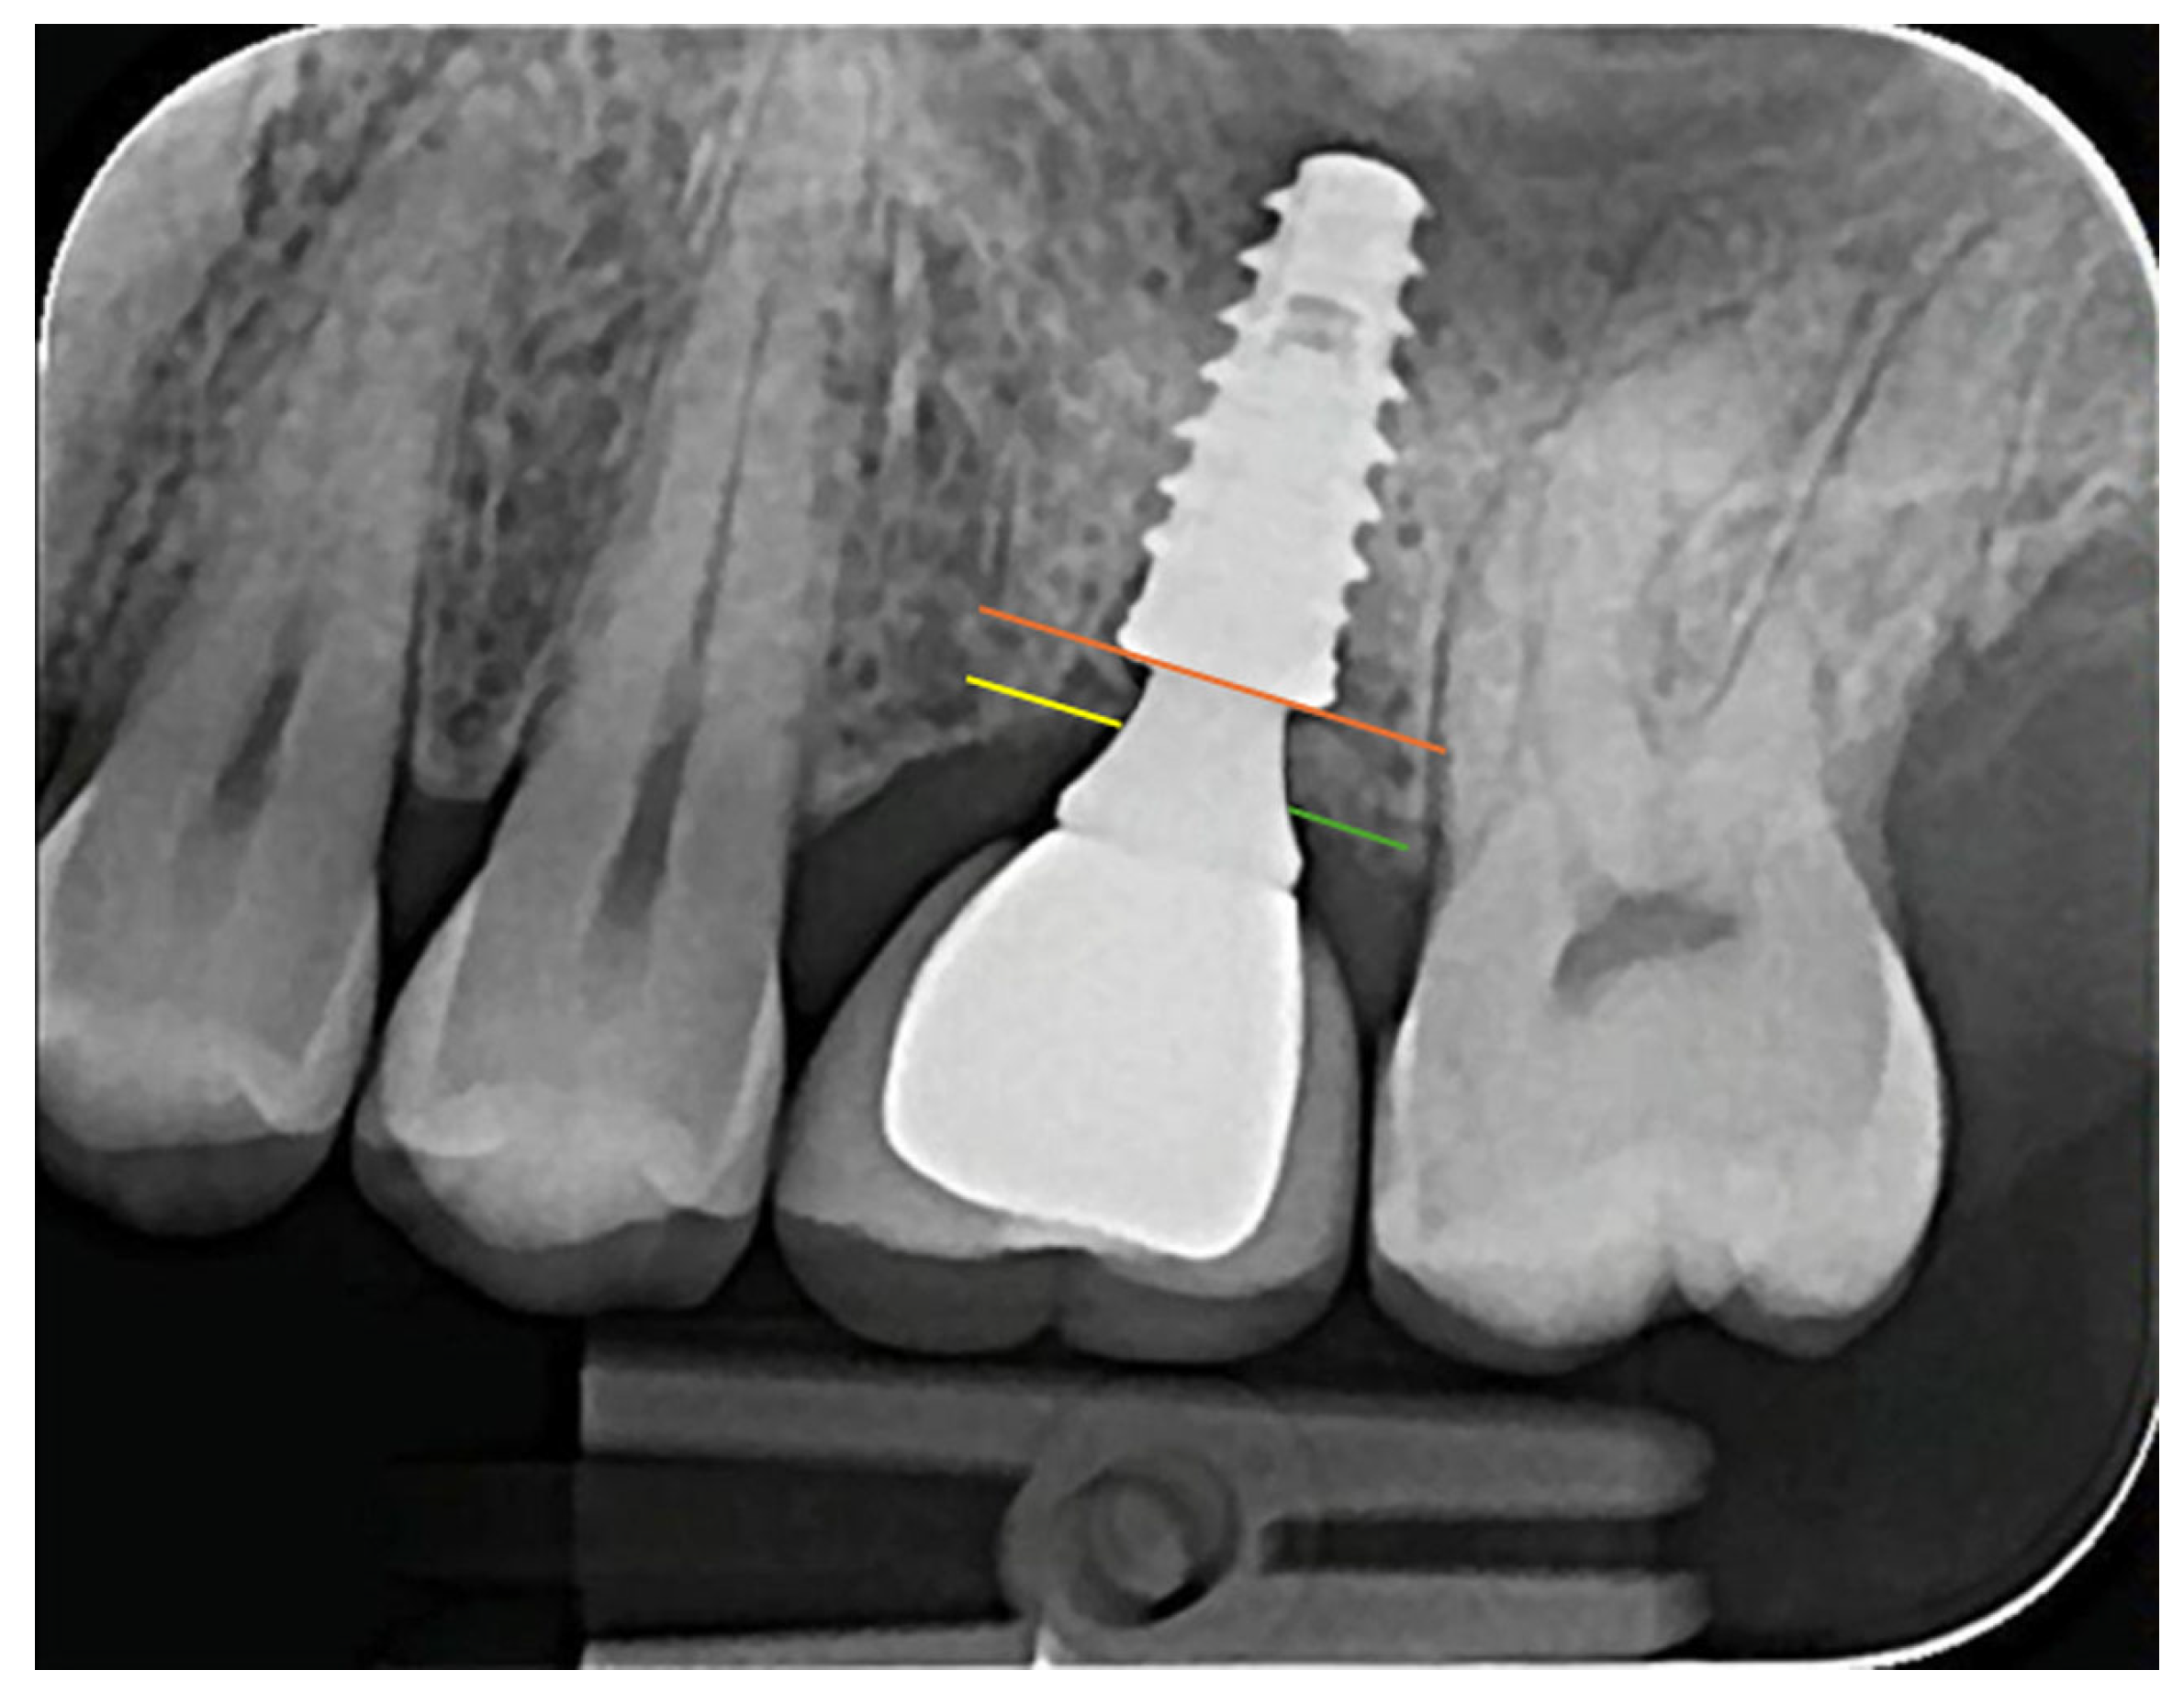

2.3.3. MBL Distance Measurement

2.3.4. Emergence Profile Measurement